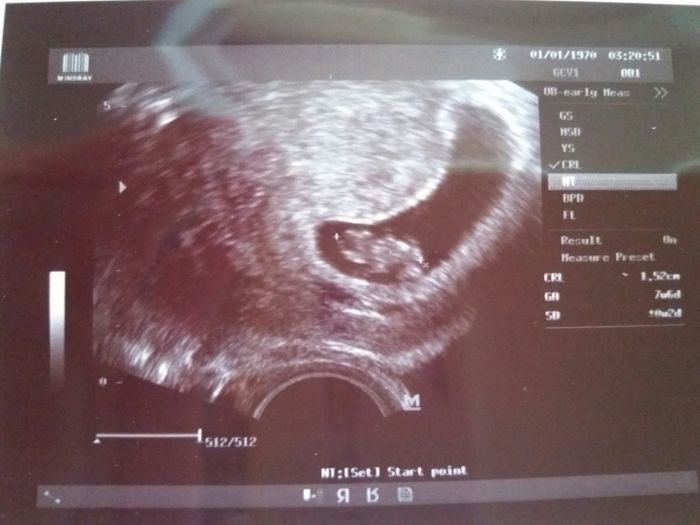

Ja dneska 7tt+6 napocitala mladsi stari pludku, ale je tam kde ma byt a bije i ❤

Posilam fotecku a Moxhi moc na tebe myslim a taky cekam jen pozitivni zpravy